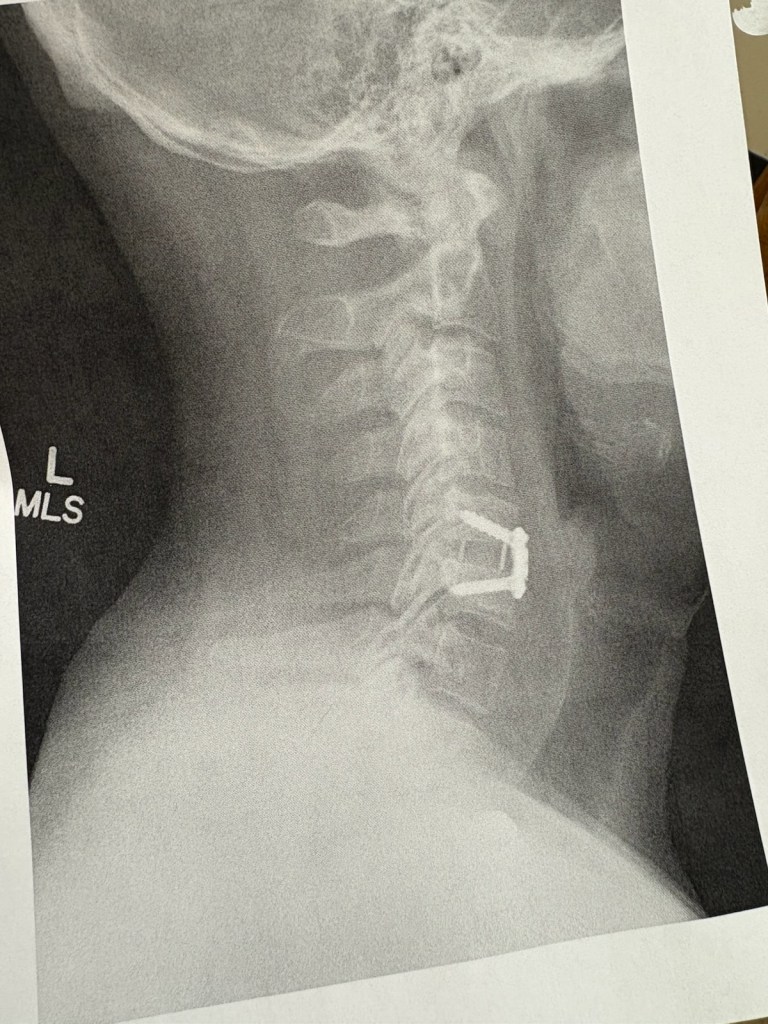

What most of you don’t know is I spent most of the year dealing with a herniated disk in my neck, and I had to take three different nerve block injections to get through the season. I ended up scheduling surgery on Oct. 28. I also fished another league this year and our season was supposed to be over before then. The last event in Florida was postponed because of Hurricane Helene and eventually rescheduled for Dec. 10 for Lake Murray.

The surgery involved some screws and replacing a bad disk. While I’m still sore in my shoulder and down my back from the surgery, the feeling in my hands has returned. Now I can focus on getting myself ready for the upcoming season.